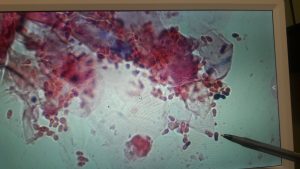

Simple ear infections detected early, often respond well to 2 weeks of treatment. A full-body exam and cytology of ear debris should be done to determine the cause of the infection (Yeast versus Bacteria versus Mites) and determine the appropriate treatment. A progress exam should be done every 2 weeks until the infection is cleared to determine when treatment should be discontinued. Ear rinsing and ear hygiene at home will help prevent another infection.

Chronic ongoing ear infections, infections of several weeks or longer, require more aggressive testing and treatment. In some cases, these may have been painful and swollen for some time without being obvious. Or these may be ear infections that come back on a regular basis. These cases require a microscopic exam, and ear culture to determine the correct antibiotic. Ongoing ear infections often have resistant bacteria as the cause, so it is essential that they are recultured to make sure the infection is gone. Many of these cases also have Otitis Media, a Middle Ear Infection. Middle ear infections require oral medication in order to penetrate the deeper tissues of the middle ear. It is important to schedule an ear flush procedure as part of the treatment to remove infectious material and allow ear drops to be more effective.